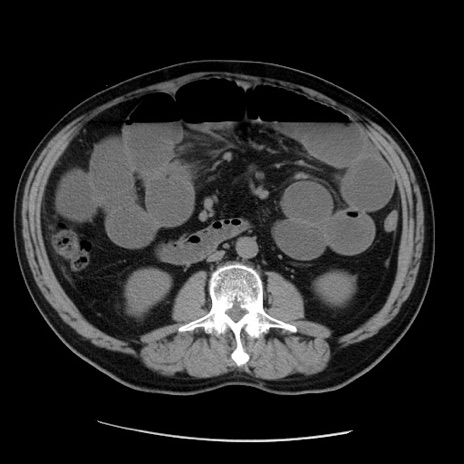

症例20(横断像)

【症例】 60歳代男性

【主訴】 腹部膨満、嘔吐

【現病歴】5日前頃より倦怠感を認め食事量減少し4日前の朝嘔吐、食事摂取困難となった。 3日前近医受診し点滴施行され整腸剤などを処方された。 当日他院を受診し、腹部膨満著明、炎症反応の上昇(CRP10.8、WBC11200)あり、紹介受診となる。

【身体所見】 意識JCS1 受け答えがはっきりしないBP 111/57mHg、 P 67bpm、、BT35.2°C、SpO2 97%(RA)、 腹部:膨隆、打診で鼓音あり、全体的に圧痛有り、腸蠕動音(-)、反跳痛ははっきりせず。

【データ】WBC 11400、CRP 14.20